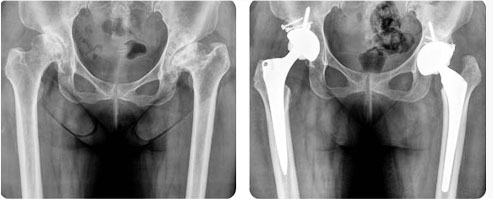

본원에서는 최신의 수술 기법과 인공 관절 기구(최소 절개 수술법, 대형 세라믹 대퇴 골두 치환술, 고도굴곡형 인공 슬관절 치환술)를 사용하여 연간 200명 이상의 환자들에게 통증없는 생활로의 전환을 도와드리고 있습니다.

인공 고관절(엉덩이) 치환술이란?

우측 퇴행성 고관절염 및 좌측 선청성 고관절 변형

- 32mm 대형 세라믹 골두 인공 고관절 전치환술 및 자가골 이식술 시행